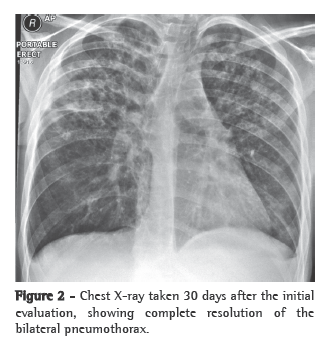

The patient was submitted to autopsy, and the cause of death was found to be total obstruction of the mitral valve within the left atrium, as shown in Figure 2. In the left lung, there were four small (3- to 6-mm) metastases that had not been detected in the preoperative period. The finding of a "cord" of tumor tissue wrapped in the mitral valve chordae and connected to the intra-atrial mass suggests that the metastasis found within the atrium was still attached to the primary tumor. With manipulation, this "cord" broke, and the metastasis migrated to the valve. Other autopsy findings were microscopic tumor emboli in the liver, kidneys and brain, probably due to embolism during surgery.